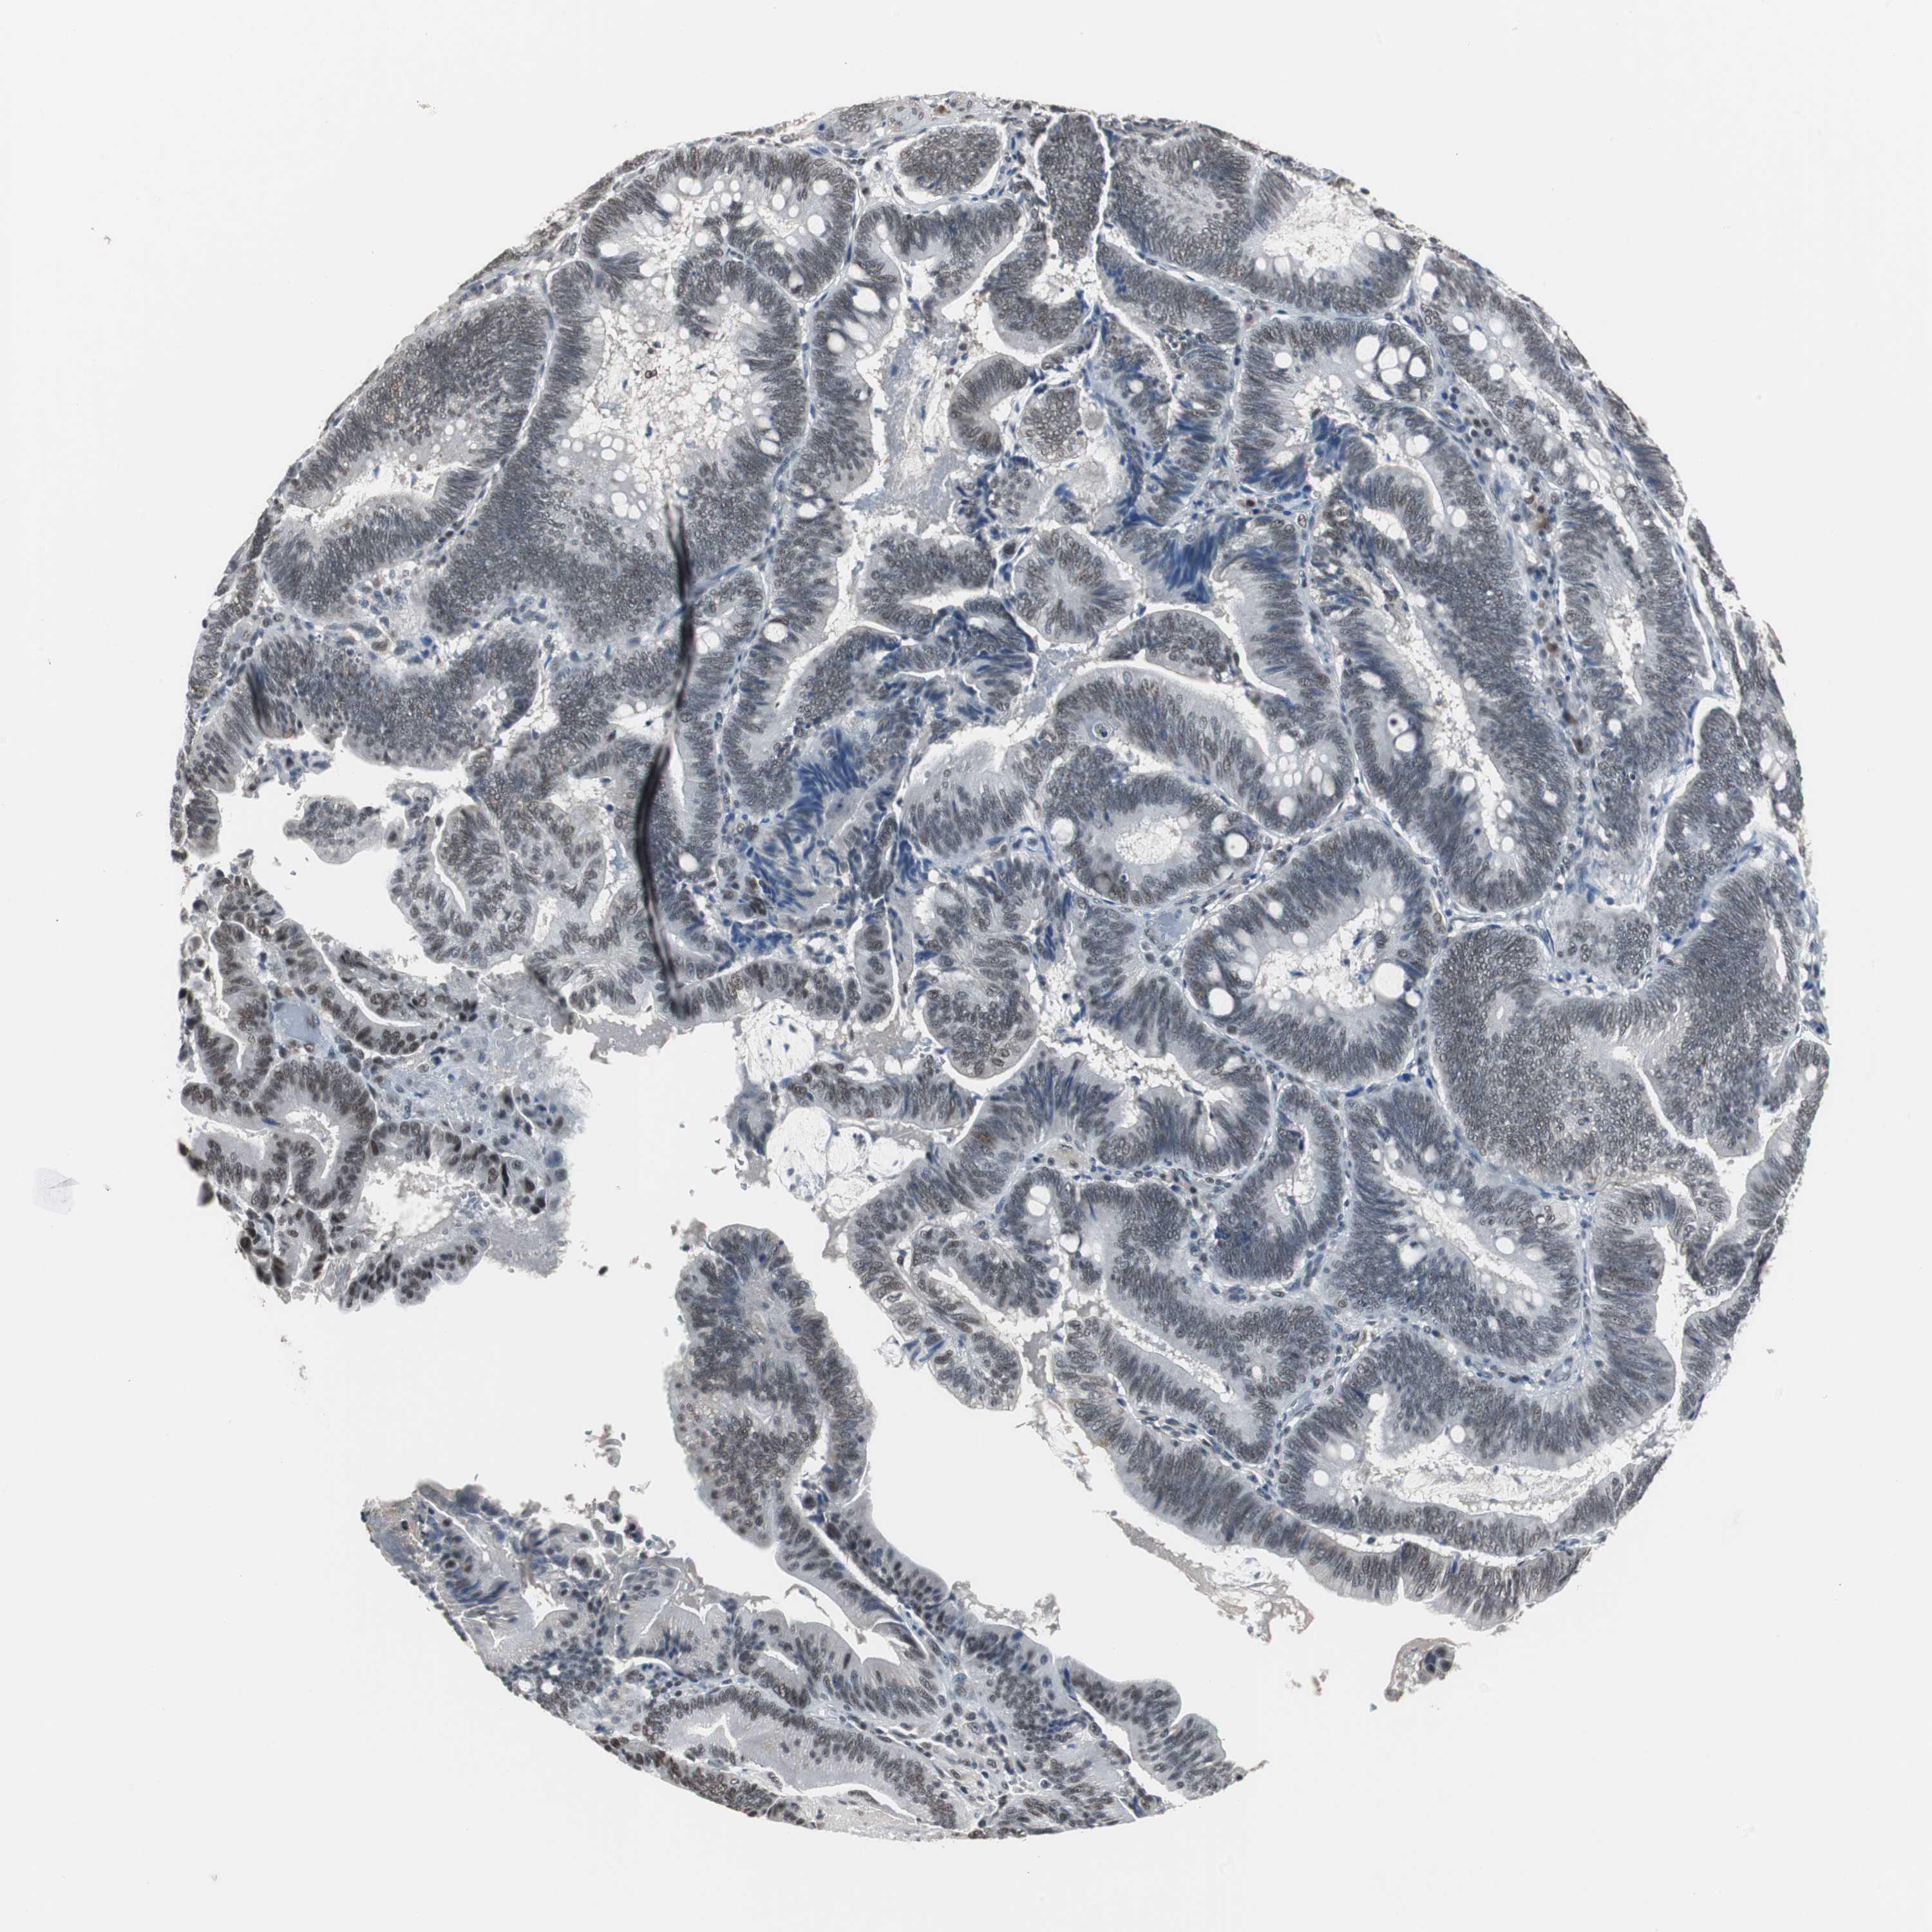

PANCREATIC CANCER - Protein expressioni

A mouse-over function shows sample information and annotation data. Click on an image to view it in a full screen mode. Samples can be filtered based on level of antibody staining by selecting one or several of the following categories: high, medium, low and not detected. The assay and annotation is described here.

Note that samples used for immunohistochemistry by the Human Protein Atlas do not correspond to samples in the TCGA dataset.

Antibody stainingi

Antibody staining in the annotated cell types in the current human tissue is reported as not detected, low, medium, or high, based on conventional immunohistochemistry profiling in selected tissues. This score is based on the combination of the staining intensity and fraction of stained cells.

Each image is clickable and will lead to virtual microscopy that enables deeper exploration of all samples and also displays staining intensity scores, fraction scores and subcellular localization as well as patient and tissue information for each sample.

Antibody HPA006429

Staining

High

Medium

Low

Not detected

Intensity

Strong

Moderate

Weak

Negative

Quantity

>75%

75%-25%

<25%

None

Location

Nuclear

Cytoplasmic/membranous

Cytoplasmic/membranous,nuclear

Adenocarcinoma, NOS

Adenocarcinoma, metastatic, NOS